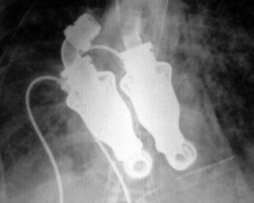

Як передає телеканал Россия 24, до цього його тестували тільки на тваринах. Особливість апарату в тому, що він переганяє кров безперервним потоком. Тобто, у людини немає серцебиття, у неї не можна виміряти пульс.

Щоб забезпечити нормальний кровообіг, звичайні апарати штучного серця повинні скорочуватися понад мільйон разів на день, через що вони часто ламаються. Тому і виникла потреба створити принципово новий імплантат.